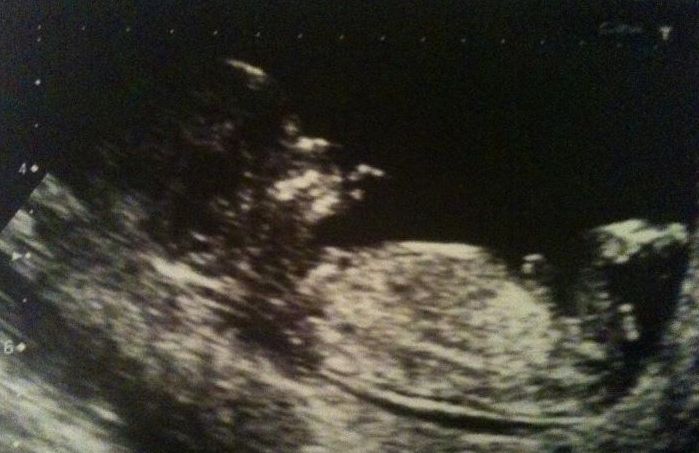

I have my 12 week scan on Monday, if mine and the midwifes calculations are right then it should say I'm 13+1 weeks. I'm hoping I'm in luck and I'm further on, I may cry if they give me anything less then 12. Just itching to get these first 15/16 weeks out of the way and get down to enjoying this pregnancy like I should be.